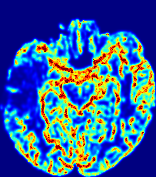

LesionRefer to captionRefer to captionRefer to captionRefer to captionRefer to captionRefer to caption𝐕rgbsubscript𝐕𝑟𝑔𝑏{\bf{V}}_{rgb}Refer to captionRefer to captionRefer to captionRefer to captionRefer to captionRefer to caption𝐕2subscriptnorm𝐕2{\|\bf{V}}\|_{2}Refer to captionRefer to captionRefer to captionRefer to captionRefer to captionRefer to captionRefer to caption3.53.53.52.82.82.82.12.12.11.41.41.40.70.70.70.00.00.0(mm/s)𝑚𝑚𝑠(mm/s)D𝐷DRefer to captionRefer to captionRefer to captionRefer to captionRefer to captionRefer to captionRefer to caption0.0200.0200.0200.0160.0160.0160.0120.0120.0120.0080.0080.0080.0040.0040.0040.0000.0000.000(mm2/s)𝑚superscript𝑚2𝑠(mm^{2}/s)Slice #1Slice #2Slice #3Slice #4Slice #5Slice #6

Figure 3: PIANO feature maps for one stroke patient, where the lesion is located in the left hemisphere. Top row: segmented stroke lesion region (white) on different slices, obtained from ISLES 2017. The corresponding slices for the PIANO feature maps are shown in the following rows.

For a better insight into an estimated velocity field 𝐕𝐕{\bf{V}} and diffusion field 𝐃𝐃{\bf{D}}, we compute the following maps: (1) 𝐕rgbsubscript𝐕𝑟𝑔𝑏{\bf{V}}_{rgb}: Color-coded orientation map of 𝐕=(Vx,Vy,Vz)T𝐕superscriptsuperscript𝑉𝑥superscript𝑉𝑦superscript𝑉𝑧𝑇{\bf{V}}=(V^{x},V^{y},V^{z})^{T}, obtained by normalizing 𝐕𝐕{\bf{V}} to unit length and mapping its 3 components to red, green, blue respectively; (2) 𝐕2subscriptnorm𝐕2\|{\bf{V}}\|_{2}: 222 norm of 𝐕𝐕{\bf{V}}; (3) D𝐷D: scalar field in Eq. 5.

Fig. 3 and Fig. 4 show the PIANO feature maps estimated from two ISLES 2017 patients: all are highly consistent with the lesion in both cases. Details of the blood flow trajectories are revealed in 𝐕rgbsubscript𝐕𝑟𝑔𝑏{\bf{V}}_{rgb} by the ridged patterns and the sharp changes of colors in the unaffected (right) hemisphere, while the flat patterns appearing within the lesion provide little directional information about the velocity and indicate low velocity magnitudes. Velocity magnitudes are more directly visualized via 𝐕2subscriptnorm𝐕2\|{\bf{V}}\|_{2}, from which one can easily locate the lesion where 𝐕2subscriptnorm𝐕2\|{\bf{V}}\|_{2} is low. D𝐷D also indicates lower diffusion values in the lesion, though with less contrast potentially due to the fact that it captures the accumulated effect of CA diffusion at the voxel-level.